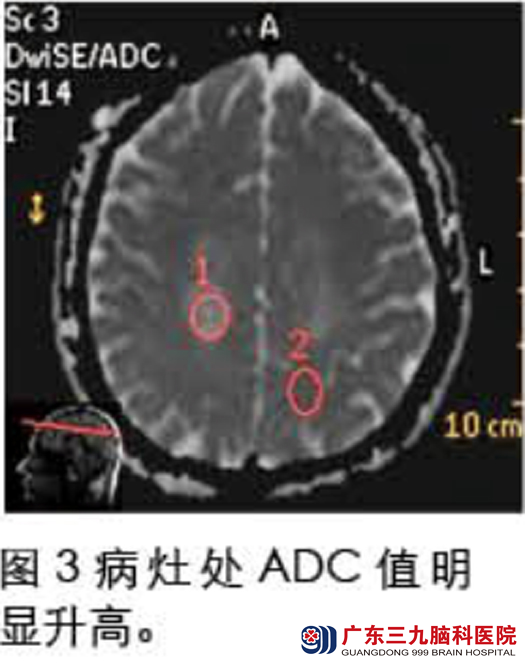

入院查体见双下肢肌力减退,肌张力偏高,腱反射亢进。头部磁共振检查示:双侧半卵圆中心多个长T1长T2病灶(见图1),伴强化(见图2),DWI序列ADC值升高(图3),MRS提示Cho峰稍有升高,NAA峰有所下降,Cr峰未见明显变化,可见Lip/Lac峰(见图4);腰穿结果:脑脊液常规正常,生化提示蛋白升高,寡克隆带阳性。确诊为Balo同心圆硬化,给予激素冲击、营养神经治疗。治疗后复查头部磁共振提示:颅内多发病灶范围较前明显缩小,异常强化程度较前减轻(见图5)。入院治疗一个月后林先生好转出院。www.999brain.com

广东三九脑科医院神经内二科主任称,Balo同心圆硬化是一种罕见的以白质髓鞘脱失区与髓鞘保存区呈特征性的洋葱皮样相间排列为特征的中枢神经系统脱髓鞘疾病,病因尚不清楚。1997年Sekijima 提出诊断同心圆硬化的必备条件是:进行性加重的大脑损害症状;MRI上在T1WI呈洋葱头样黑白相间的类圆形病灶,呈等、低信号,中心呈更低信号,为髓鞘严重脱失及坏死带;T2WI/FLAIR像呈等、高信号交替环,周缘可见晕环征象,为病灶周围轻度水肿表现,亦称“煎鸡蛋征”。本例磁共振表现符合以上特点。www.999brain.com